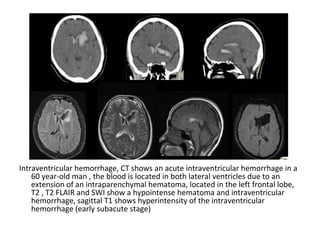

-Artery of Percheron is a variant where there is a

dominant thalamic perforator supplying the

ventromedial thalami bilaterally and the rostral

midbrain arising from a P1 PCA segment , an artery

of Percheron infarct will result in bilateral

ventromedial thalamic infarction with (pattern 1) or

without (pattern 2) midbrain infarction (the infarct

may be V-shaped if the midbrain is involved , deep

venous thrombosis may also result in bilateral

thalamic infarcts

DSA of the left vertebral injection , lateral (A) and anteroposterior (B) views

and a coronal CTA image (C) show a large unpaired thalamic perforating

artery (arrows) arising from the proximal P1 segment supplying the

bilateral thalami (i.e. Artery of Percheron)

FLAIR at the level the thalamus (A & C) and midbrain (B & D) show bilateral

paramedian thalamic and midbrain involvement (pattern 1), notice the

hyperintense signal intensity along the pial surface of the midbrain

interpeduncular fossa representing the V sign (B and D)

Axial FLAIR (A and B) and DWI (C and D) images at the level of the thalamus

(A & C) and midbrain (B & D) demonstrate infarction of the bilateral

paramedian thalami without midbrain involvement (pattern 2)

Axial FLAIR through the midbrain show a V-shaped hyperintense signal

intensity along the pial surface of the midbrain at the interpeduncular

fossa (the V sign)